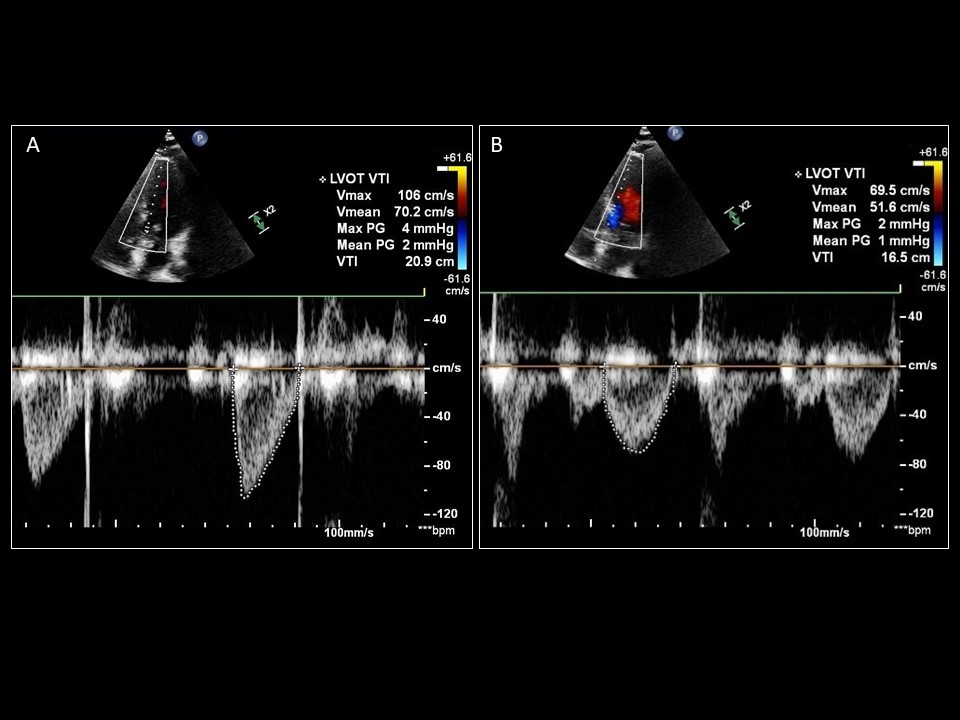

LVOT VTI generated when the Doppler line of interrogation is (A) parallel to blood flow versus (B) off-axis by greater than 20˚

Sattin, Burhani, Jaidka, Arntfield. How I Do It: Echocardiographic-based Stroke Volume and Cardiac Output Determination. CHEST.